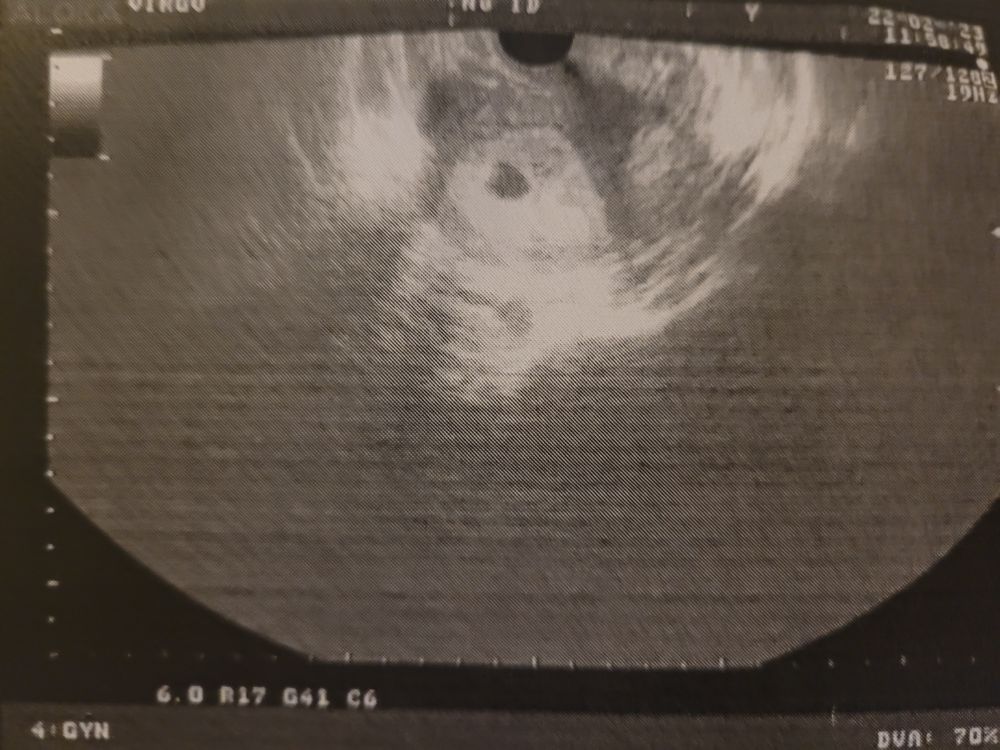

Вы что? Круг серый это мешочек этот, а внутри черненькое пятнышко это будущий ребенок

Анастасия, ну вот как я понимаю, чёрное это плодное яйцо, а в нём должен быть жм😅

Настасья, снимок конечно не очень хорошего качества)),я подумала,чтотсерое это пя)))

Елена Л, срок ещё совсем маленький и узист не нашёл жм, но я вижу его внутри чёрного плодного яйца, но может и мерещится конечно 😔

Черное это плодное яйцо, и всего остального там пока нет, так как оно очень маленькое ещё. Жм будет как шарик в контурами внутри, лично я пока его не вижу. Какой срок у вас? Возможно ещё очень рано.

Di , узист ставит 4 недели, но плодное яйцо 8 мм, мне кажется большевато для такого срока

Настасья, Изображение По таблице свд 8 мм соответствует 4.1 недели беременности, при 5% процентиле

Контуры жм есть вроде.